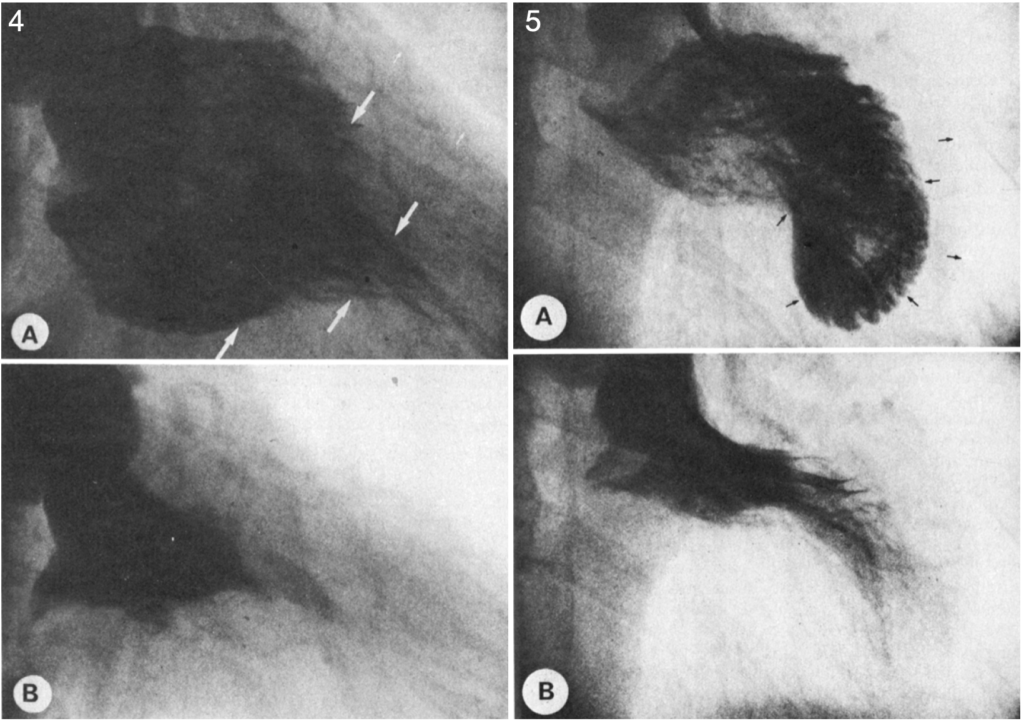

Ventriculogram

5: Left ventriculograms in hypertrophic obstructive cardiomyopathy at (A) end-diastole the free wall is equally thickened in all segments (arrows) and the left ventricular silhouette is shaped like a kidney or banana. (B), at end systole.

Yamaguchi 1979